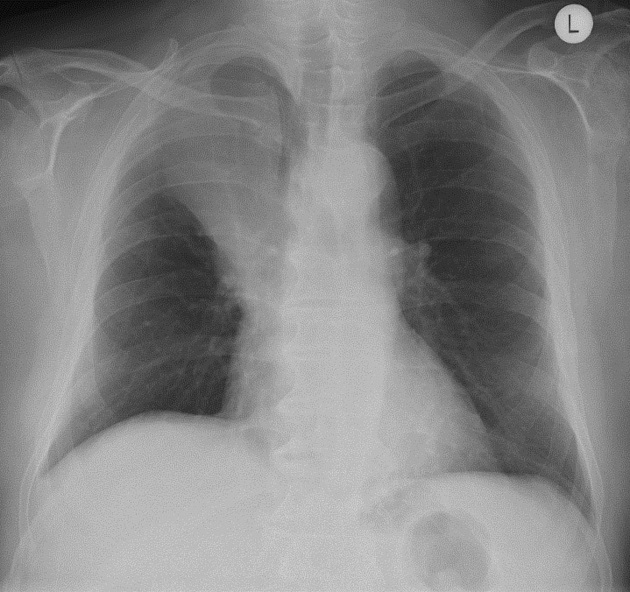

What’s going in in this CXR?

This is a postpneumonectomy patient, with the surgical clips in place.

This was taken POD1 following pneumonectomy. Over the next months, this space will slowly fill with fluid, and then over the following 3 months it will gradually fibrose. The heart and mediastinum will then shift towards this side due to myofibroblast contraction.

The patient will also be missing the 5th or 6th rib, taken as part of the procedure, and surgical clips will be present.